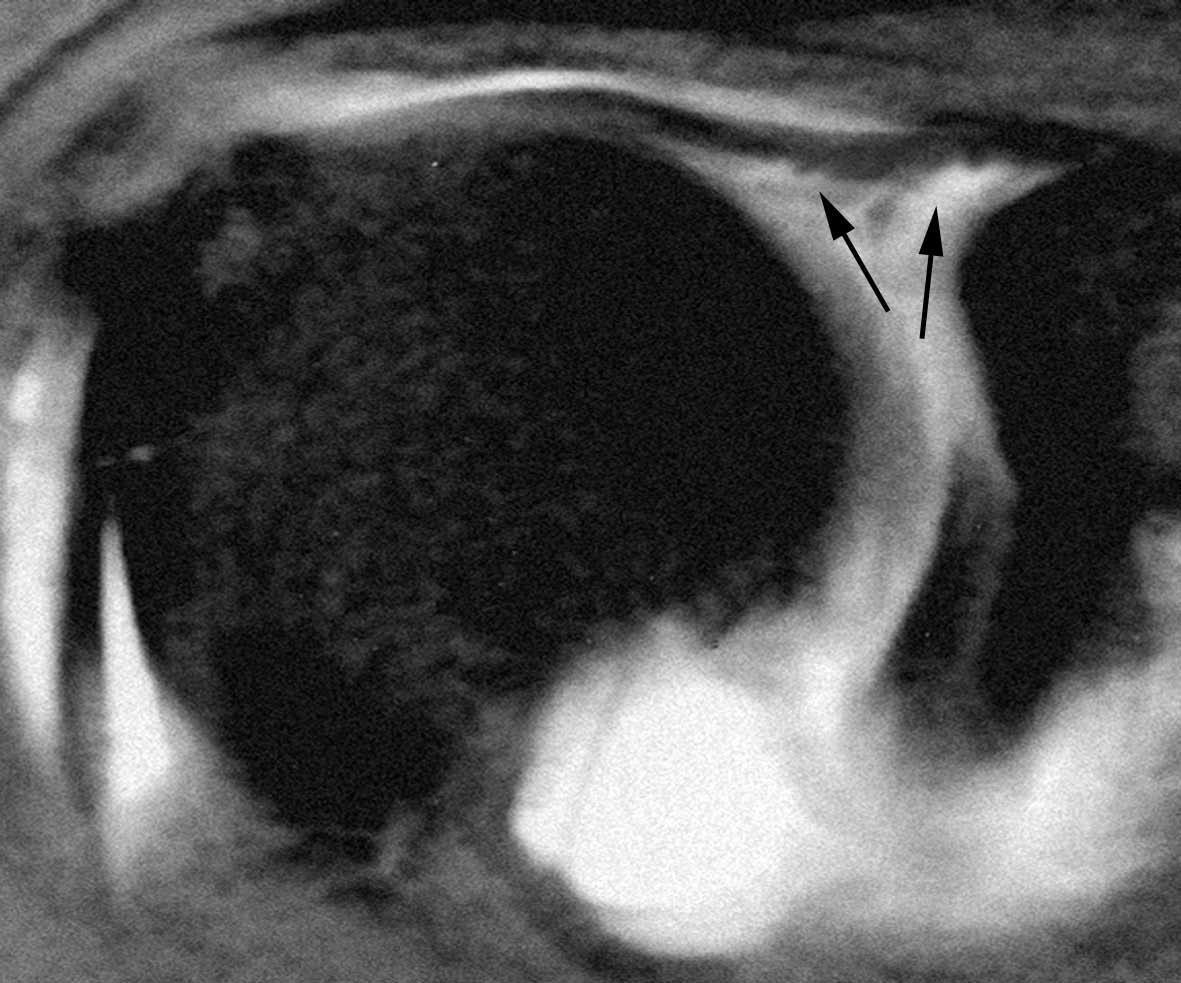

Lesiones por pinzamiento anterosuperior (anterosuperior impingement syndrome)

El síndrome de pinzamiento anterosuperior se produce durante el movimiento repetitivo de elevación anterior del brazo con rotación interna. En este síndrome se pueden producir lesiones de la polea reflectora (LGHS, TLB y LCH) así como del LG superior y de los tendones del supraespinoso y subescapular (fig. 33). Habermeyer et al29 han descrito cuatro tipos de lesiones por pinzamiento anterosuperior dependiendo de las diferentes estructuras afectadas.

Fig. 33.--Síndrome de pinzamiento anterosuperior (ASI). Resonancia magnética (RM) axial GRE (A) y coronal oblicua DP (densidad protónica) (B) que revela una rotura del ligamento glenohumeral superior (LGHS) (flechas en A) y una lesión SLAP (superior labrum anterior posterior) tipo II (flecha en B).

En general, este tipo de lesiones son semejantes a las lesiones que afectan al intervalo MR, con la diferencia de que las primeras son por lesión repetitiva y crónica, mientras que las segundas son por traumatismo agudo.